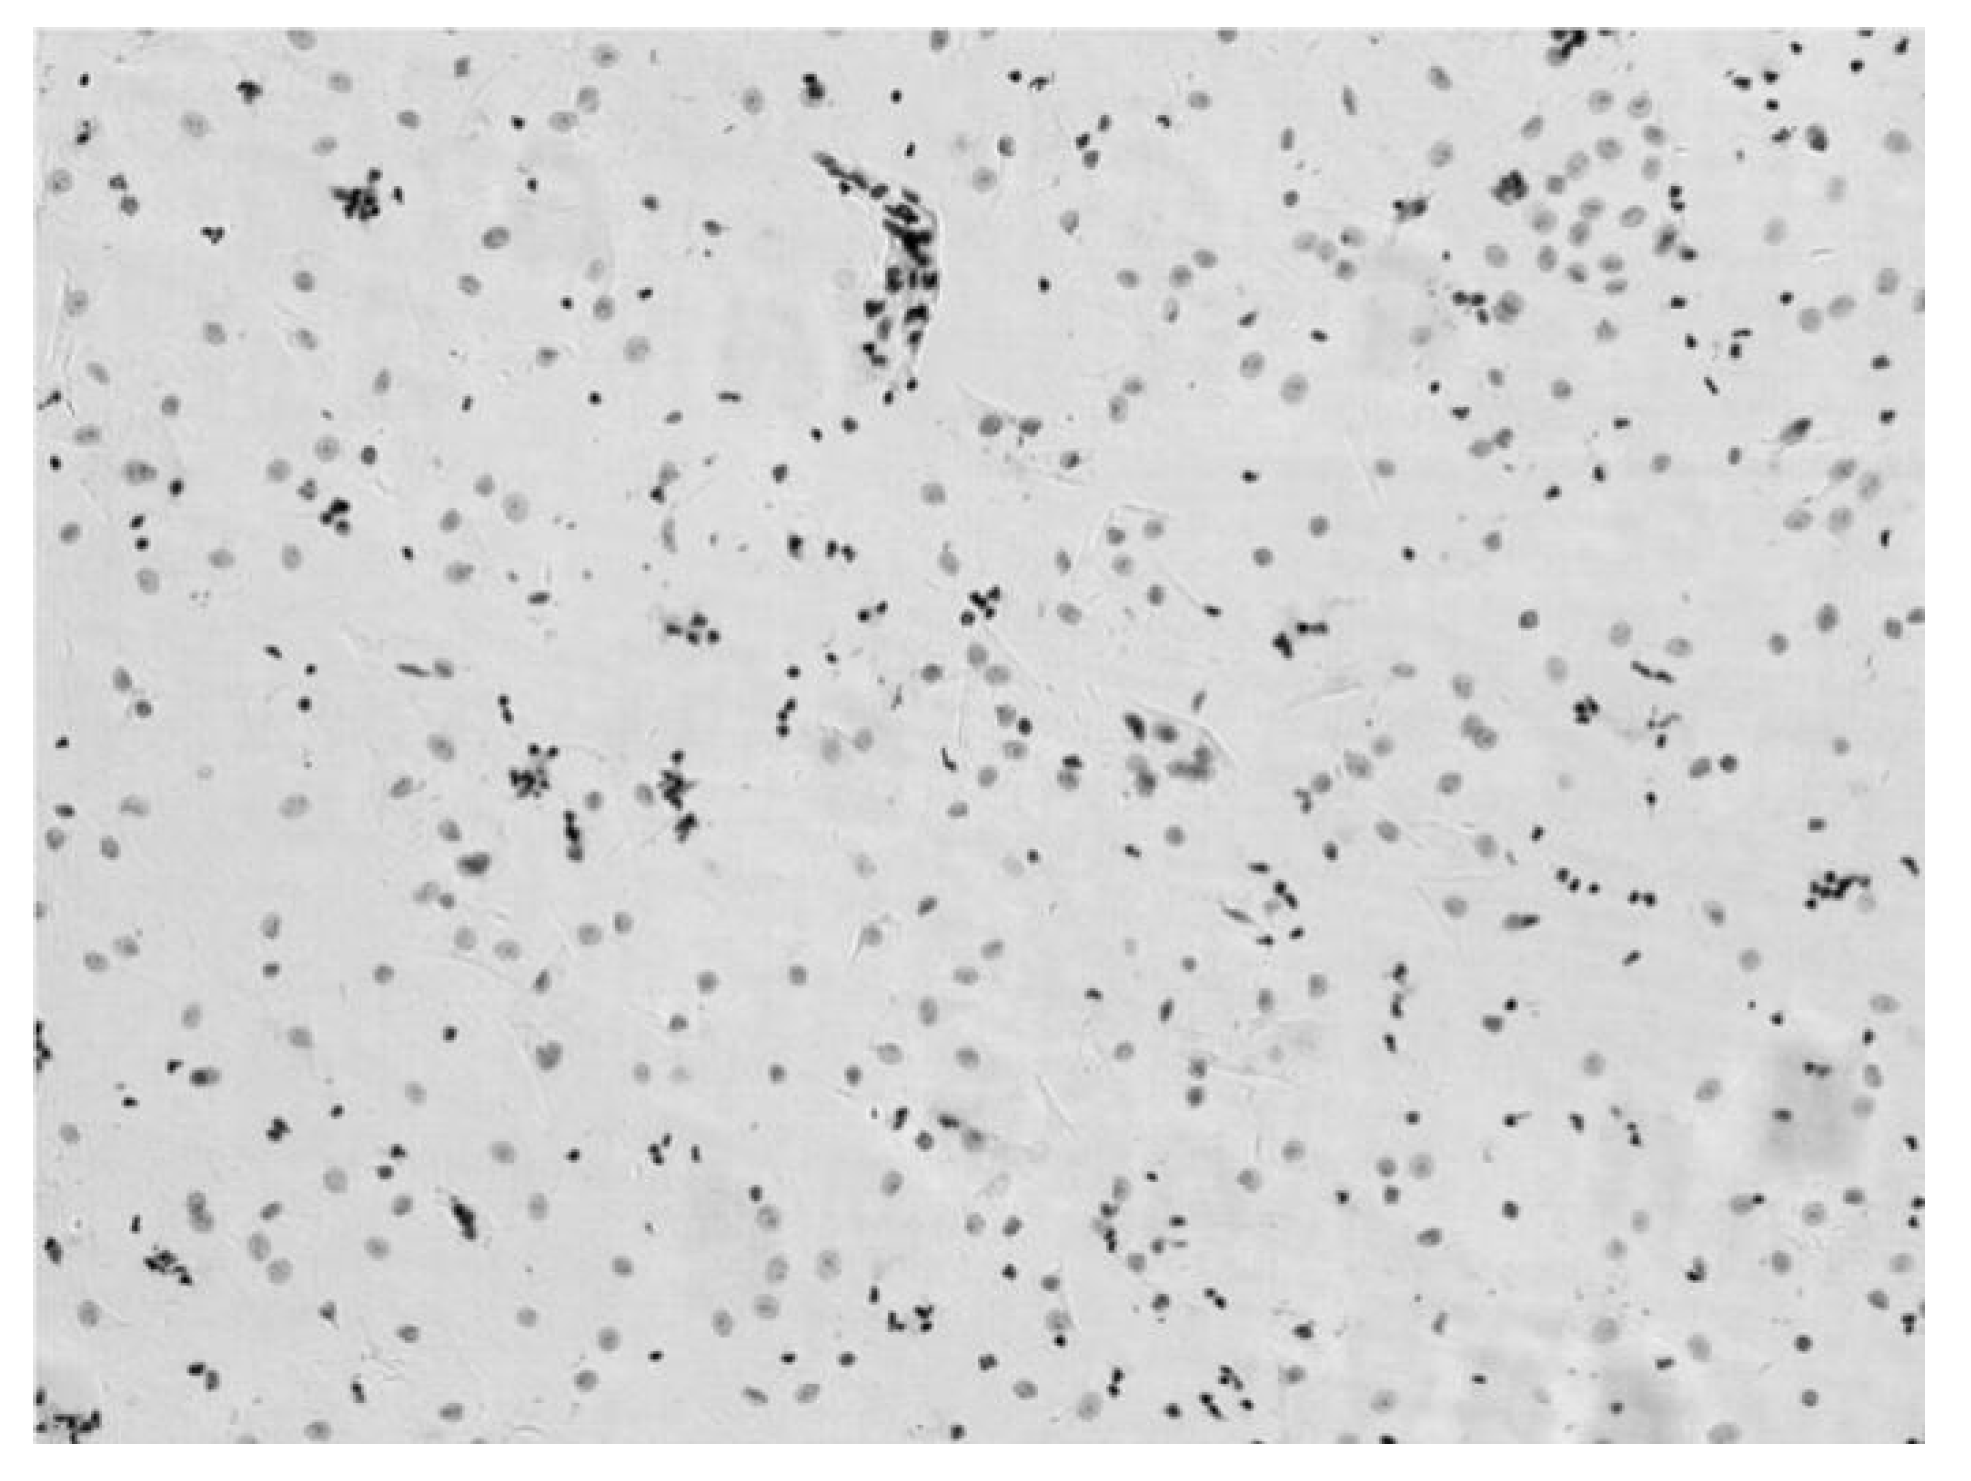

3.2. Verification Test of DNA Quantitative Analysis

3.3. The Performance of Cervical Cell Screening